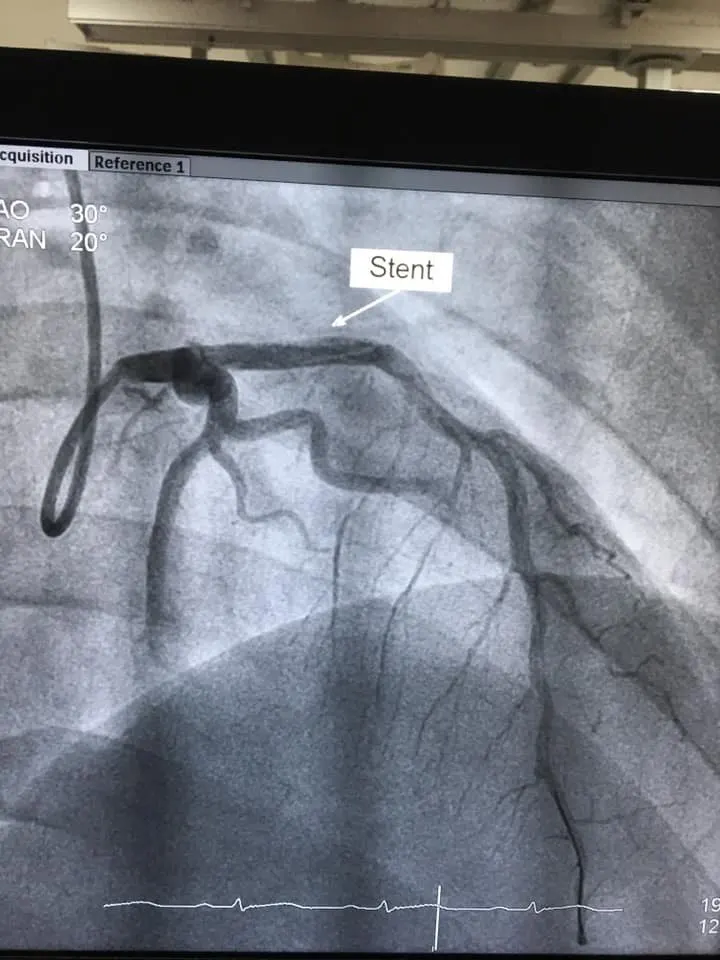

ผู้ป่วยชาย อายุ 23ปี สูบบุหรี่

แน่นหน้าอก 15นาที ก่อนมาโรงพยาบาล

ฉีดสีหลอดเลือดหัวใจพบลิ่มเลือดอุดตันหลอดเลือดด้านซ้าย ได้รับการทำบอลลูนใส่ขดลวด

เพิ่งเสร็จเมื่อสักครู่